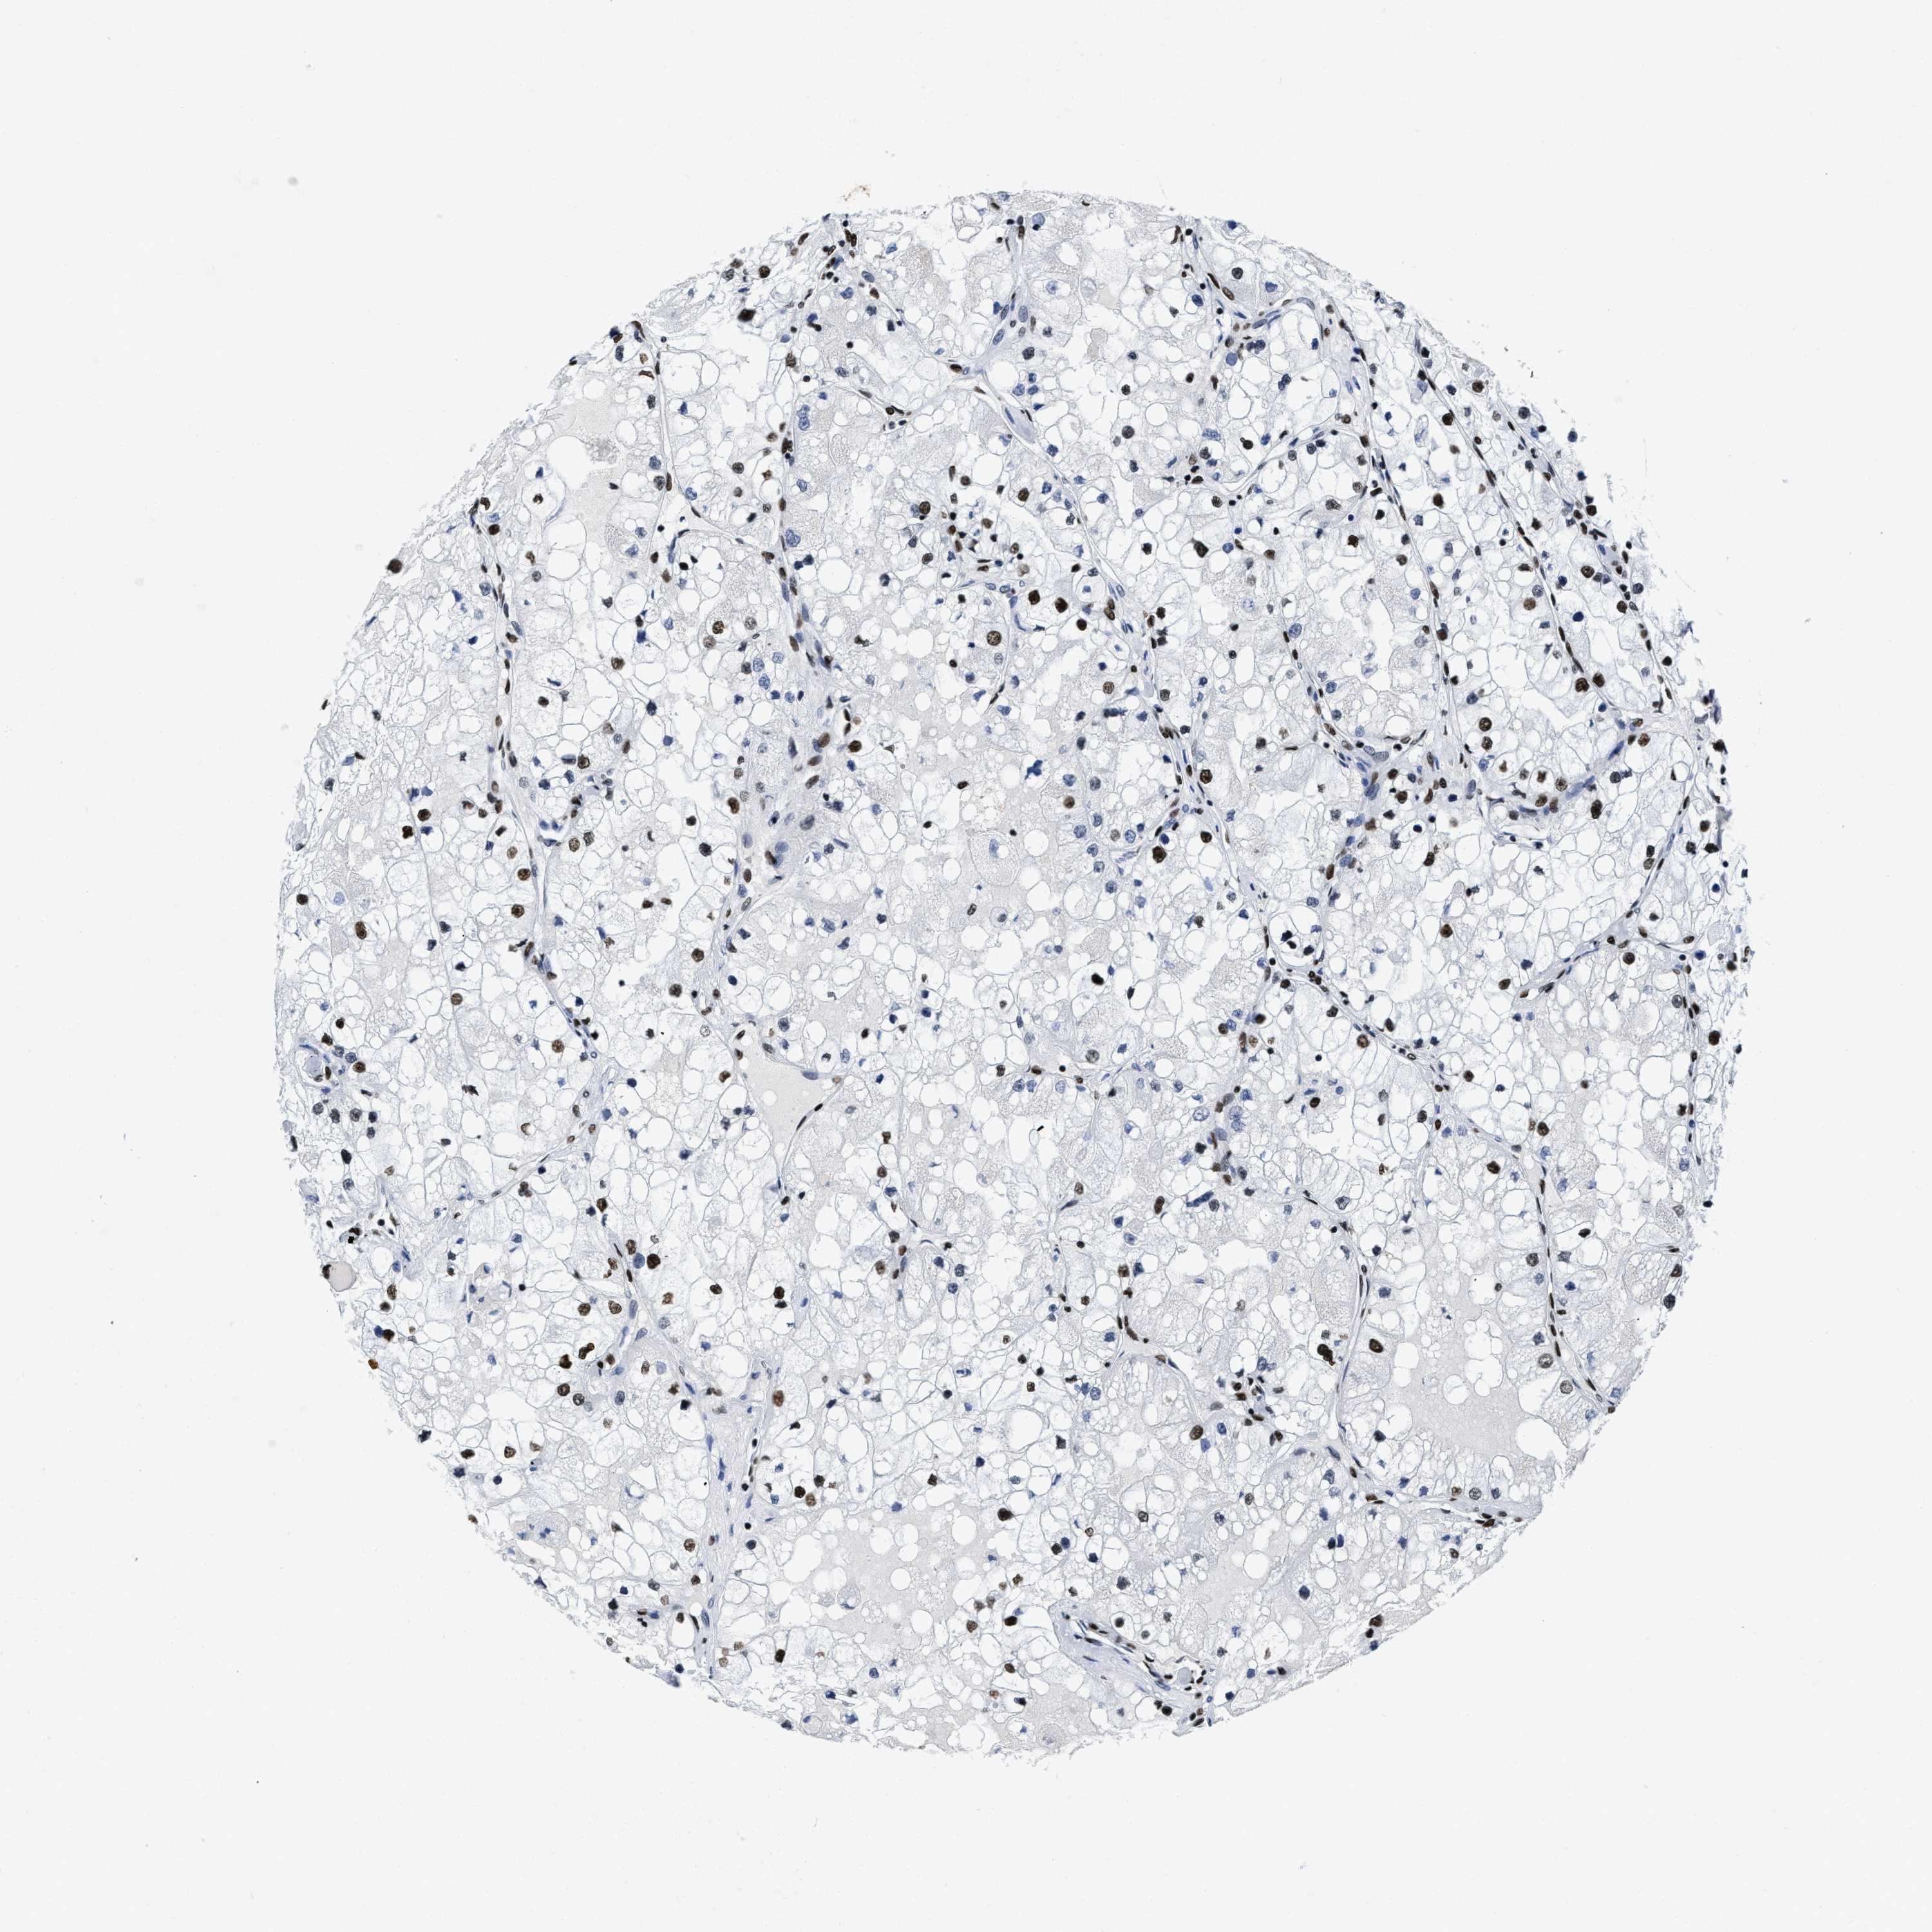

KIDNEY RENAL PAPILLARY CELL CARCINOMA (TCGA) - Interactive survival scatter ploti

The Survival Scatter plot shows the clinical status (i.e. dead or alive) for all individuals in the patient cohort, based on the same data that underlies the corresponding Kaplan-Meier plots. Patients that are alive at last time for follow-up are shown in blue and patients who have died during the study are shown in red.

The x-axis shows the expression levels (FPKM) of the investigated gene in the tumor tissue at the time of diagnosis. The y-axis shows the follow-up time after diagnosis (years). Both axes are complimented with kernel density curves demonstrating the data density over the axes. The top density plot shows the expression levels (FPKM) distribution among dead (red) and alive patients (blue). The right density plot shows the data density of the survived years of dead patients with high and low expression levels respectively, stratified using the cutoff indicated by the vertical dashed line through the Survival Scatter plot. This cutoff is automatically defined based on the FPKM cutoff that minimizes the p-score. The cutoff can be changed by dragging the vertical line or by entering a cutoff value in the square labeled "Current cut-off".

Under the Survival Scatter plot the p-score landscape (black curve; left axis) is shown together with dead median separation (red curve; right axis). Dead median separation is the difference in median mRNA expression between patients who have died with high and low expression, respectively. It is calculated as follows: median FPKM expression of dead patients with high expression - median FPKM expression of dead patients with low expression. This is intended to aid the user in visually exploring custom cutoffs and the associated p-scores and dead median separation.

Individual patient data is displayed and can be filtered by clicking on one or more of the category buttons on the top of the page. Categories describing expression level and patient information include: high, low, alive, dead, female, male and tumor stages. The scale of the x-axis can be toggled between linear and log-scale by clicking on the "x log" button. Mouse-over function shows TCGA ID, patient information and mRNA expression (FPKM) for each patient.

& Survival analysisi

Kaplan-Meier plots summarize results from analysis of correlation between mRNA expression level and patient survival. Patients were divided based on level of expression into one of the two groups "low" (under cut off) or "high" (over cut off). X-axis shows time for survival (years) and y-axis shows the probability of survival, where 1.0 corresponds to 100 percent.

SMARCC2 is not prognostic in Kidney Renal Papillary Cell Carcinoma (TCGA)

Best expression cut offi

Based on the FPKM value of each gene, patients were classified into two groups and association between prognosis (survival) and gene expression (FPKM) was examined. The best expression cut-off refers the FPKM value that yields maximal difference with regard to survival between the two groups at the lowest log-rank P-value. Best expression cut-off was selected based on survival analysis .

When clicking on this number, the vertical dashed line indicating cut-off, the interactive survival plot, and the Kaplan-Meier curve will be adjusted to show results based on the best expression cut-off.

: 60.45

Median expressioni

Median expression refers to the median FPKM value calculated based on the gene expression (FPKM) data from all patients in this dataset. When clicking on this number, the vertical dashed line indicating cut-off, the interactive survival plot, and the Kaplan-Meier curve will be adjusted to show results based on the median expression.

: N/A

Median follow up timei

Median follow up time refers to the median time (years) after diagnosis with this type of cancer, based on clinical data from all patients in this dataset.

P scorei

Log-rank P value for Kaplan-Meier plot showing results from analysis of correlation between mRNA expression level and patient survival.

N/A

5-year survival highi

5-year survival for patients with higher expression than the expression cutoff.

For melanoma and glioma, 3-year survival is shown.

5-year survival lowi

5-year survival for patients with lower expression than the expression cutoff.

TCGA RNA samplesi

RNA-seq data is reported as average FPKM (number Fragments Per Kilobase of exon per Million reads), generated by the The Cancer Genome Atlas (TCGA) .

Normal distribution across the dataset is visualized with box plots, shown as median and 25th and 75th percentiles. Points are displayed as outliers if they are above or below 1.5 times the interquartile range. FPKM values of the individual samples are presented next to the box plot.